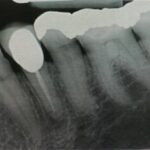

Perfekte Wurzelfüllung

Eine Wurzelbehandlung in unserer modernen Zahnarztpraxis in Bielefeld erstreckt sich meist über mehrere Sitzungen und ist sehr zeitaufwändig. Ein Aufwand, der sich lohnt: bereits beherdete Zähne mit kleineren Entzündungen erhalten die Chance zur Regeneration und Ausheilung, unbeherdete „frische“ Zähne können so für den Organismus neutral bleiben. Ganzheitliche Belastungen werden vermieden.